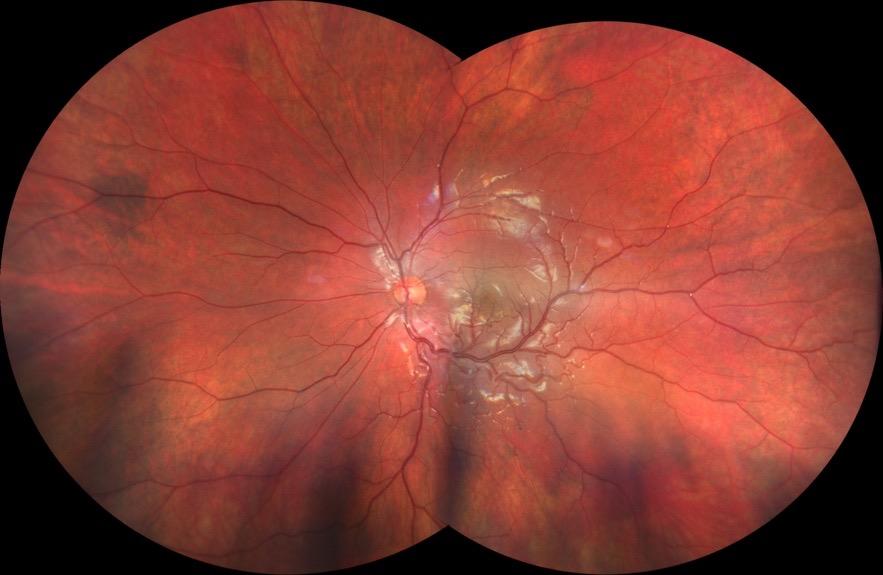

Figure 2. Multimodal imaging of right eye of a male diabetic patient affected by PDR and DME. 2A-B) UWF pseudocolor retinography (Optos Silverstone, Optos, UK) and corresponding magnification of macular region showing diffuse hard exudates and intraretinal hemorrages; 2C) OCT (Heidelberg Spectralis, Heidelberg Engineering Inc., Germany) displaying diffuse center-involving DME; 2D-E) Late phase UWF FA (Optos Silverstone, Optos, UK) and corresponding magnification of macular region presenting extense breakdown of BRB with perivascular leakage and non-perfusion areas, pooling effect compatible with MA and masking effect due to pre-retinal hemorrhages. Two leakage spots associated to possible NVs close to inferior vascular arcade; 2F) 3x3 B-scan OCT-A (Zeiss PLEX Elite 9000, Carl Zeiss, Germany) showing flow signal within pre-retinal NV.

Figure 3. Multimodal imaging of a male diabetic patient affected by PDR and DME that has already been treated by incomplete laser photocoagulation therapy. 3A) UWF pseudocolor retinography displaying hard exudates and intraretinal hemorrhages within vascular arcades and peripheral laser photocoagulation therapy; 3B) UWF SS-OCT showing focal center-involving DME; 3C) Late phase UWF FA (describing mild BRB disruption with 2 leakage areas compatible with NV along inferior vascular arcade; 3D) 15x15 En-face WF-SS-OCTA presenting FAZ enlargement, diffuse capillary drop-out and temporal mid-peripheral retinal nonperfusion areas, and two pathological vascular networks associated to NVs.

Figure 4. Multimodal imaging of a female diabetic patient affected by PDR that has already undergone complete laser photocoagulation treatment. 4A) UWF pseudocolor retinography showing complete laser photocoagulation treatment until vascular arcades; 4B-C) 12x12 and 4E-F) en-face WF-SS-OCTA of diabetic patient (4B, 4E) presenting FAZ enlargement, diffuse capillary drop-out and inferior mid-peripheral retinal nonperfusion areas, as compared to healthy patient (4C, 4F; 4D) Late phase UWF FA displaying diffuse BRB breakdwon, with perivascular leakage and non-perfusion areas.

5. Multimodal imaging of a

diabetic patient affected by

5A) UWF pseudocolor retinography showing some hard exudates within and outside vascular arcades; 5B) Late phase UWF FA presenting far peripheral BRB rupture, with associated perivascular leakage and retinal ischemia, and diffuse pooling effect within telengectasic vessels; 5C) UWF SS-OCT, displaying some hard exudates close to optic disc.

OCT-A) (Figures 2-5).